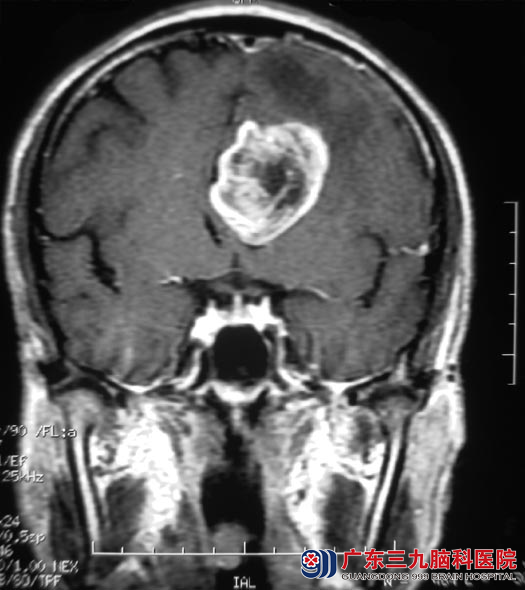

广东三九脑科医院头颅MR检查提示:左侧额叶深层白质区胼胝体上方占位病灶,范围约34.1mm×49.1mm×29.6mm,周围示大片状低信号水肿影,胼胝体明显受压,提示偏恶性肿瘤性病变,高级别星形细胞瘤或转移瘤可能。